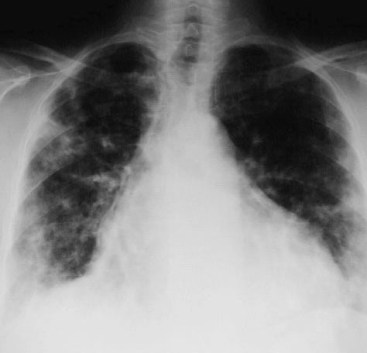

SIGNO DE LAS ALAS DE MARIPOSA INVERTIDAS

La presencia de infiltrados alveolares de disposición periférica y bilateral, respetando las regiones perihiliares, provoca una imagen opuesta a la del signo de las alas de mariposa. Este hallazgo se ve en la neumonía eosinófica.